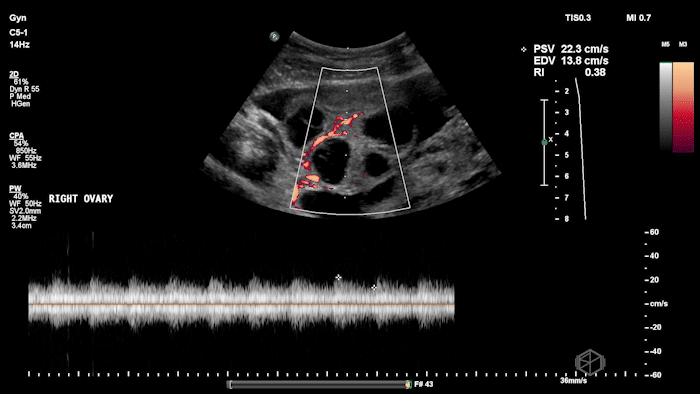

She grabbed the probe, and working with Dr. Zimmerman, saw the following:

There is moderate free fluid, no obvious pleural effusions. The bilateral ovaries are enlarged with multiple cystic structures. There are normal arterial and venous waveforms for both ovaries.

• Preserved ovarian arterial and venous flow helps distinguish OHSS from acute ovarian torsion, where flow may be compromised.